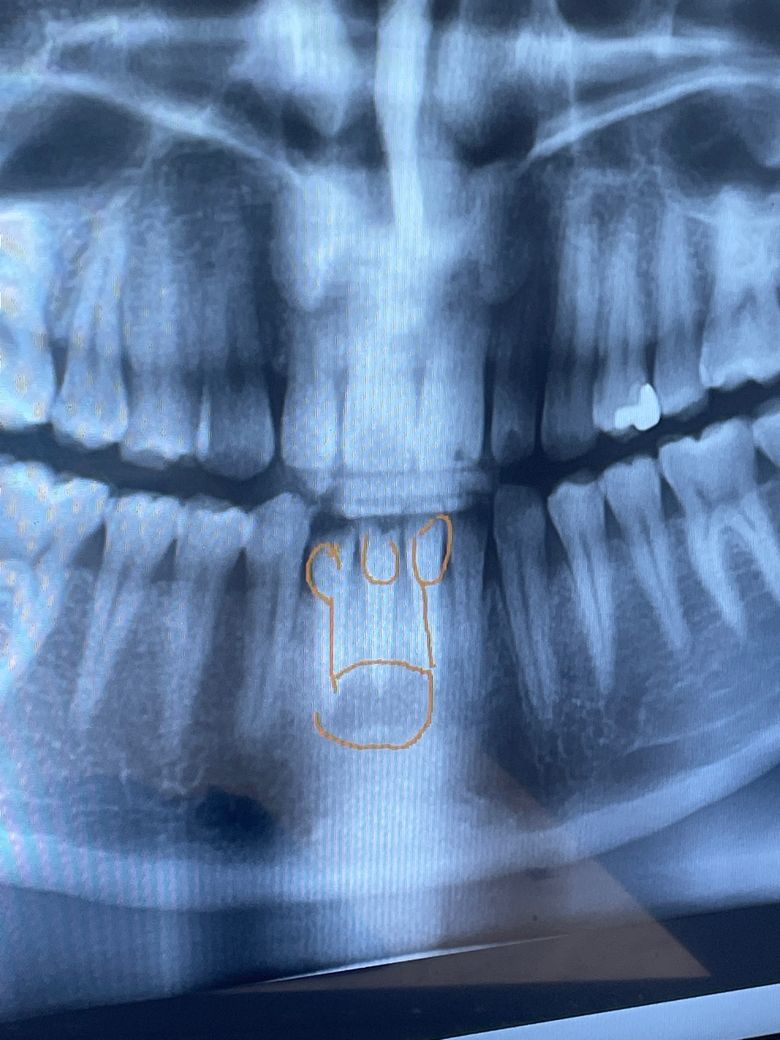

앞니 뿌리 염증이 큰데 발치를 꼭 해야하나요

어제 아침부터 아래 앞니 잇몸아래쪽부터 붇는 느낌이 나면서 압통이 있어서 확인 해 보니 잇몸안에 크게 덩어리가 생겨 부어 올라있더라고요 그래서 병원을 오늘 가보니 엑스레이에서 치아 뿌리에 염증이 커져서 잇몸뼈가 녹아서 앞니를 하나 발치를 하고 양쪽 앞니를 신경치료후 브릿지를 해야한다고 하였습니다 꼭 발치를 해야하는 걸까요... 이빨이 조금 흔들리긴 하는데 최대한 이빨을 살리고 싶습니다ㅠㅠ

• 파노라마 방사선 사진상에서 아래 앞니 뿌리끝으로 염증이 많이 퍼진 것은 사실입니다 일단 신경치료를 시도해볼 순 있으나 결과는 좋지 않을 수도 있고 구강 내 병소와 관련하여 추가적으로 구강내과에서 생검을 진행해볼 필요도 있을 것 같습니다